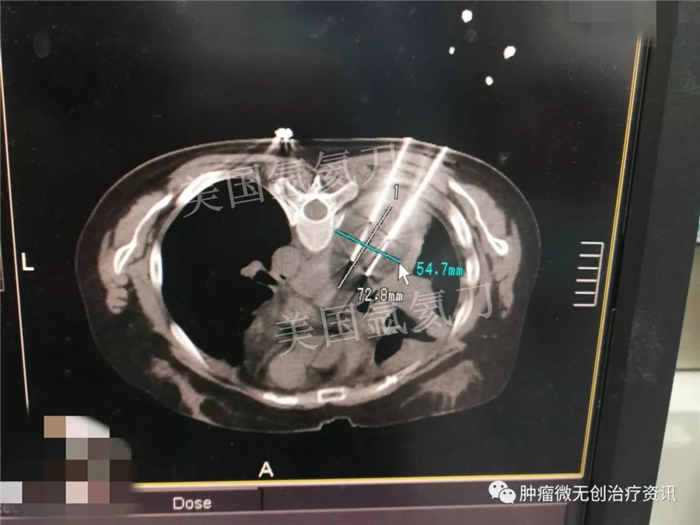

中日友好医院氩氦刀冷冻消融治疗胸膜间皮瘤

30岁女性患者,因胸膜间皮瘤,就诊于中日友好医院中西医结合肿瘤内科。结合患者情况,行氩氦刀冷冻消融治疗。此次手术的主要目标为减瘤。